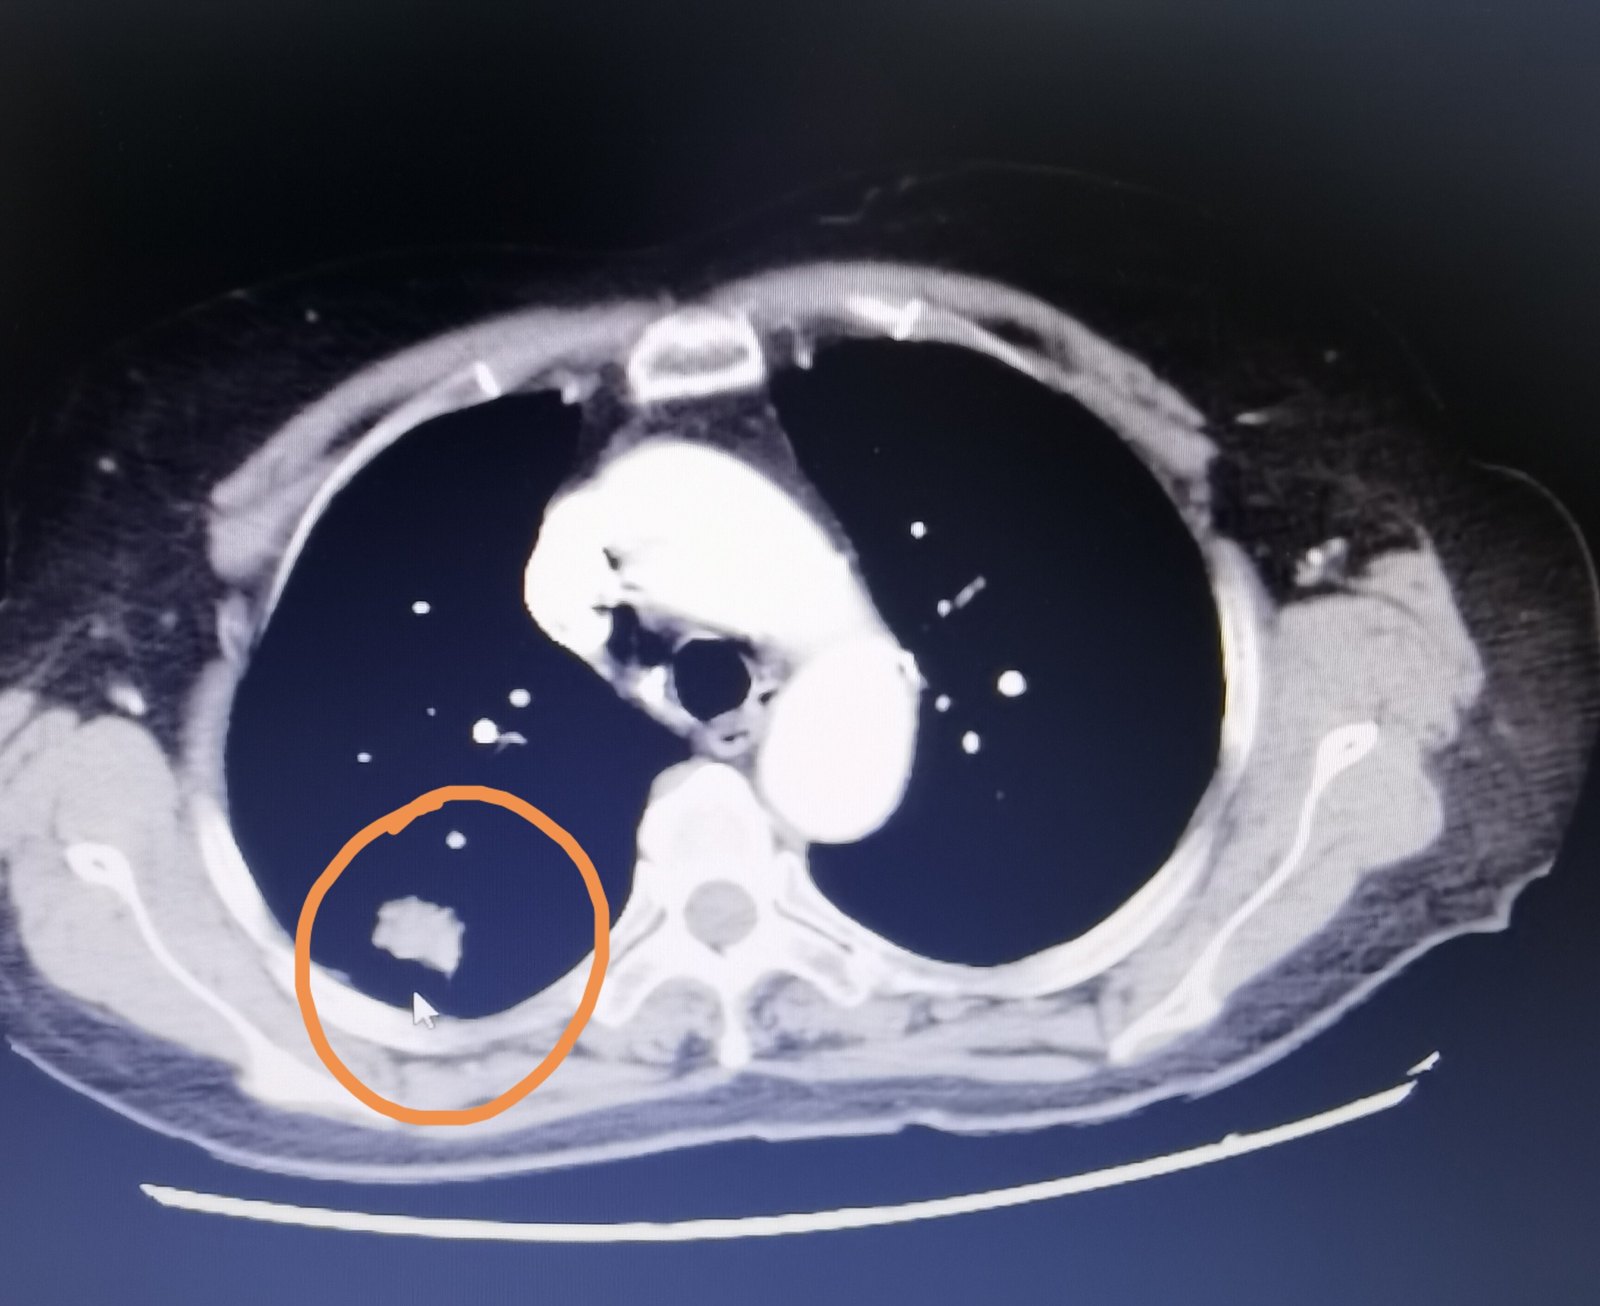

这位71岁的老爷子,驼背,近期胸背疼,胸部ct发现左下肺肿瘤,有胸膜牵拉

混合磨玻璃结节,伴有胸膜牵拉——肺腺癌

(图4)病灶周围的胸膜牵拉,影像学表现——胸膜凹陷征.

胸膜凹陷征表现为规则线条影自结节牵拉胸膜,胸膜凹入形成典型喇叭口